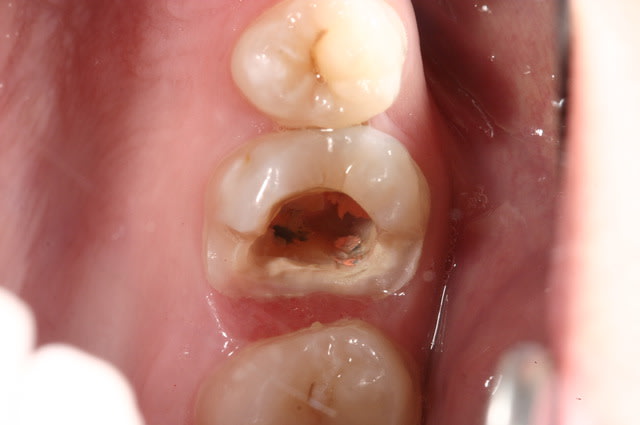

Pour abonder dans le sens qu'il ne faut pas couronner dans tous les cas, voici un cas fait il y a un an.

Les facteurs qui m'ont amené à prendre la décision de faire une endocouronne (proche d'un onlay en vérité) :

- 3 parois solides, la dernière pas trop fine.

- limites toutes supragingivales

- occlusion favorable (pas de photos de l'antagoniste je n'y ai pas pensé)

- patient réceptif

- grande profondeur de la chambre pulpaire (pas très visible sur les photos verticales)

Je n'en fais pas souvent mais quand j'en fait c’est que j'ai confiance. Faire une couronne classique ? Sur ce cas rien que de préparer les limites périphériques et on se retrouve avec une dent à raz la gencive, avec obligation de faire un (ou plusieurs) tenons longs pour une bonne rétention, générateur de fracture radiculaire....

Couronne Emax, collée au Multilink Automix

PS : avant toute remarque, non la patiente ne veut pas que je touche à sa dent de lait résiduelle ;o)

Je me rends compte que la hauteur importante des parois et de la chambres ne sont pas très visibles sur les photos : j’aurais du prendre un angle de biais pour les visualiser en terme photo.